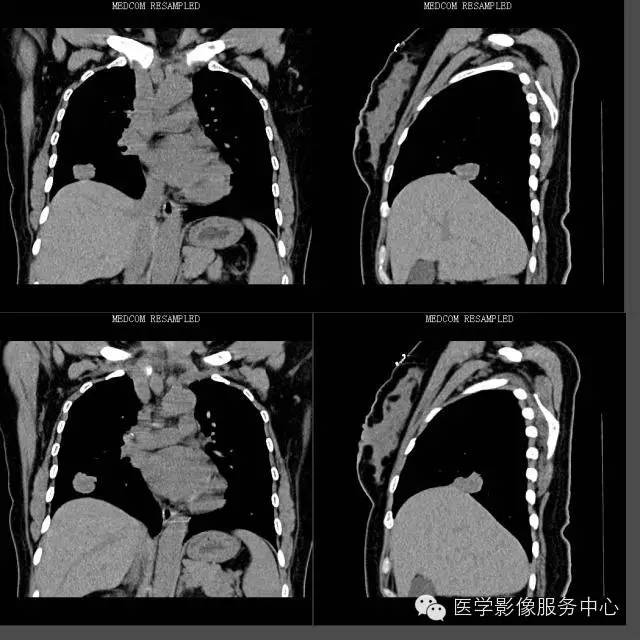

CT上表现的结节或肿块影像在病理组织学上为肿瘤的乳头状结构,以及破坏、扭曲的肺组织;磨玻璃样阴影代表肿瘤细胞沿肺泡壁生长或阻塞肺泡腔引起的阻塞性肺炎;

肺乳头状腺癌生长方式与肺泡癌相似,结节或肿块影周围出现的卫星灶能对应病理组织学上的阻塞性肺炎、支气管炎、细支气管脓肿等改变。这种磨玻璃样改变在肺腺癌病例中普遍可以看到,但在其他类型肺癌中比较少见。

“空泡征”、“空气支气管征”在肺乳头状腺癌病例中大部分可以看到,但边缘光滑、境界清楚;而其他类型肺癌即使出现这些征象,其边缘境界往往不清楚,这一点是和其他类型肿瘤所不同的。